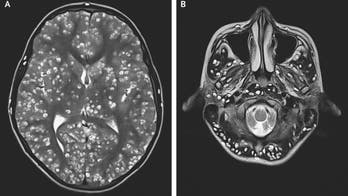

March 29, 2019 Teen suffering from seizures dies after doctors discover parasitic tapeworm eggs in his brain An 18-year-old India man, who was not identified, complained of having pain in his groin and swelling in his eye, was found to have parasites in his brain.